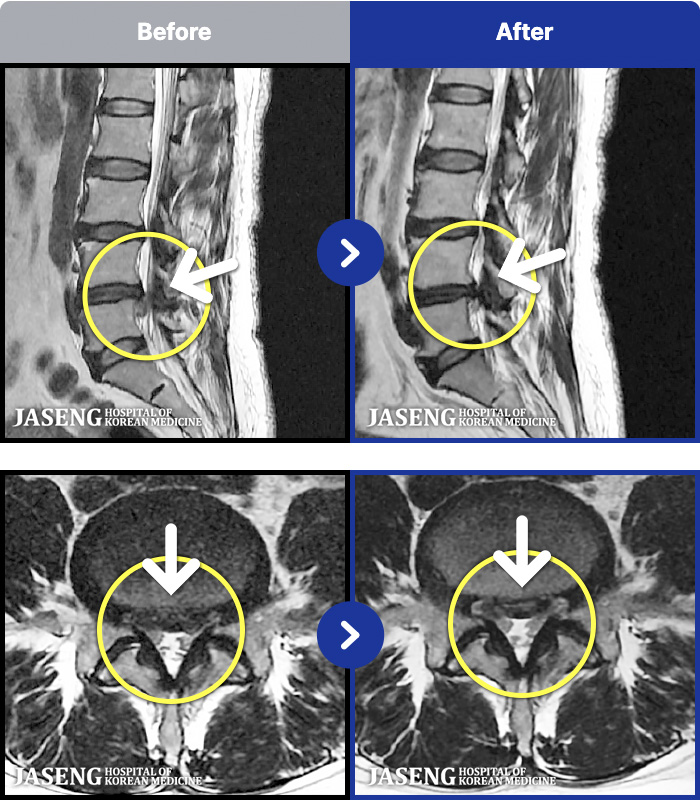

MRI ġ

1,237 MRI ũ ʸ Ȯϼ.